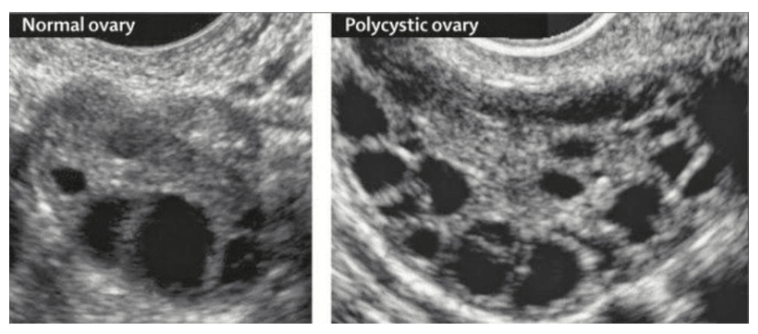

PCOS is a condition characterized by irregular or absent ovulation, elevated androgens, and the appearance of multiple small follicles on the ovaries—often described as a “string of pearls” on ultrasound.

Despite the name, these are not true cysts, but immature follicles that failed to ovulate.